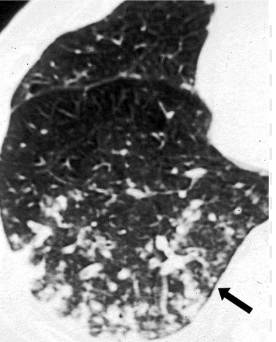

气道侵袭性曲霉菌病,右下肺外周部大小不等,结节影与分支线状影混合,分界不清